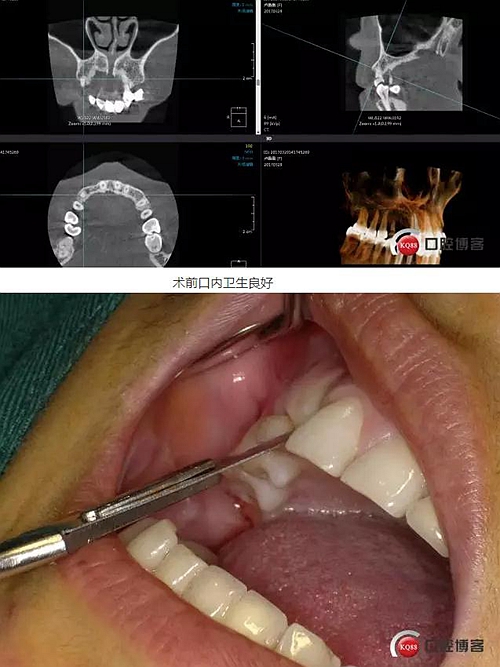

患者右上二缺失,CT示唇腭向骨量不足,右上3為乳牙滯留且骨量足設(shè)計(jì)右上三即拔即種手術(shù)

術(shù)前ct